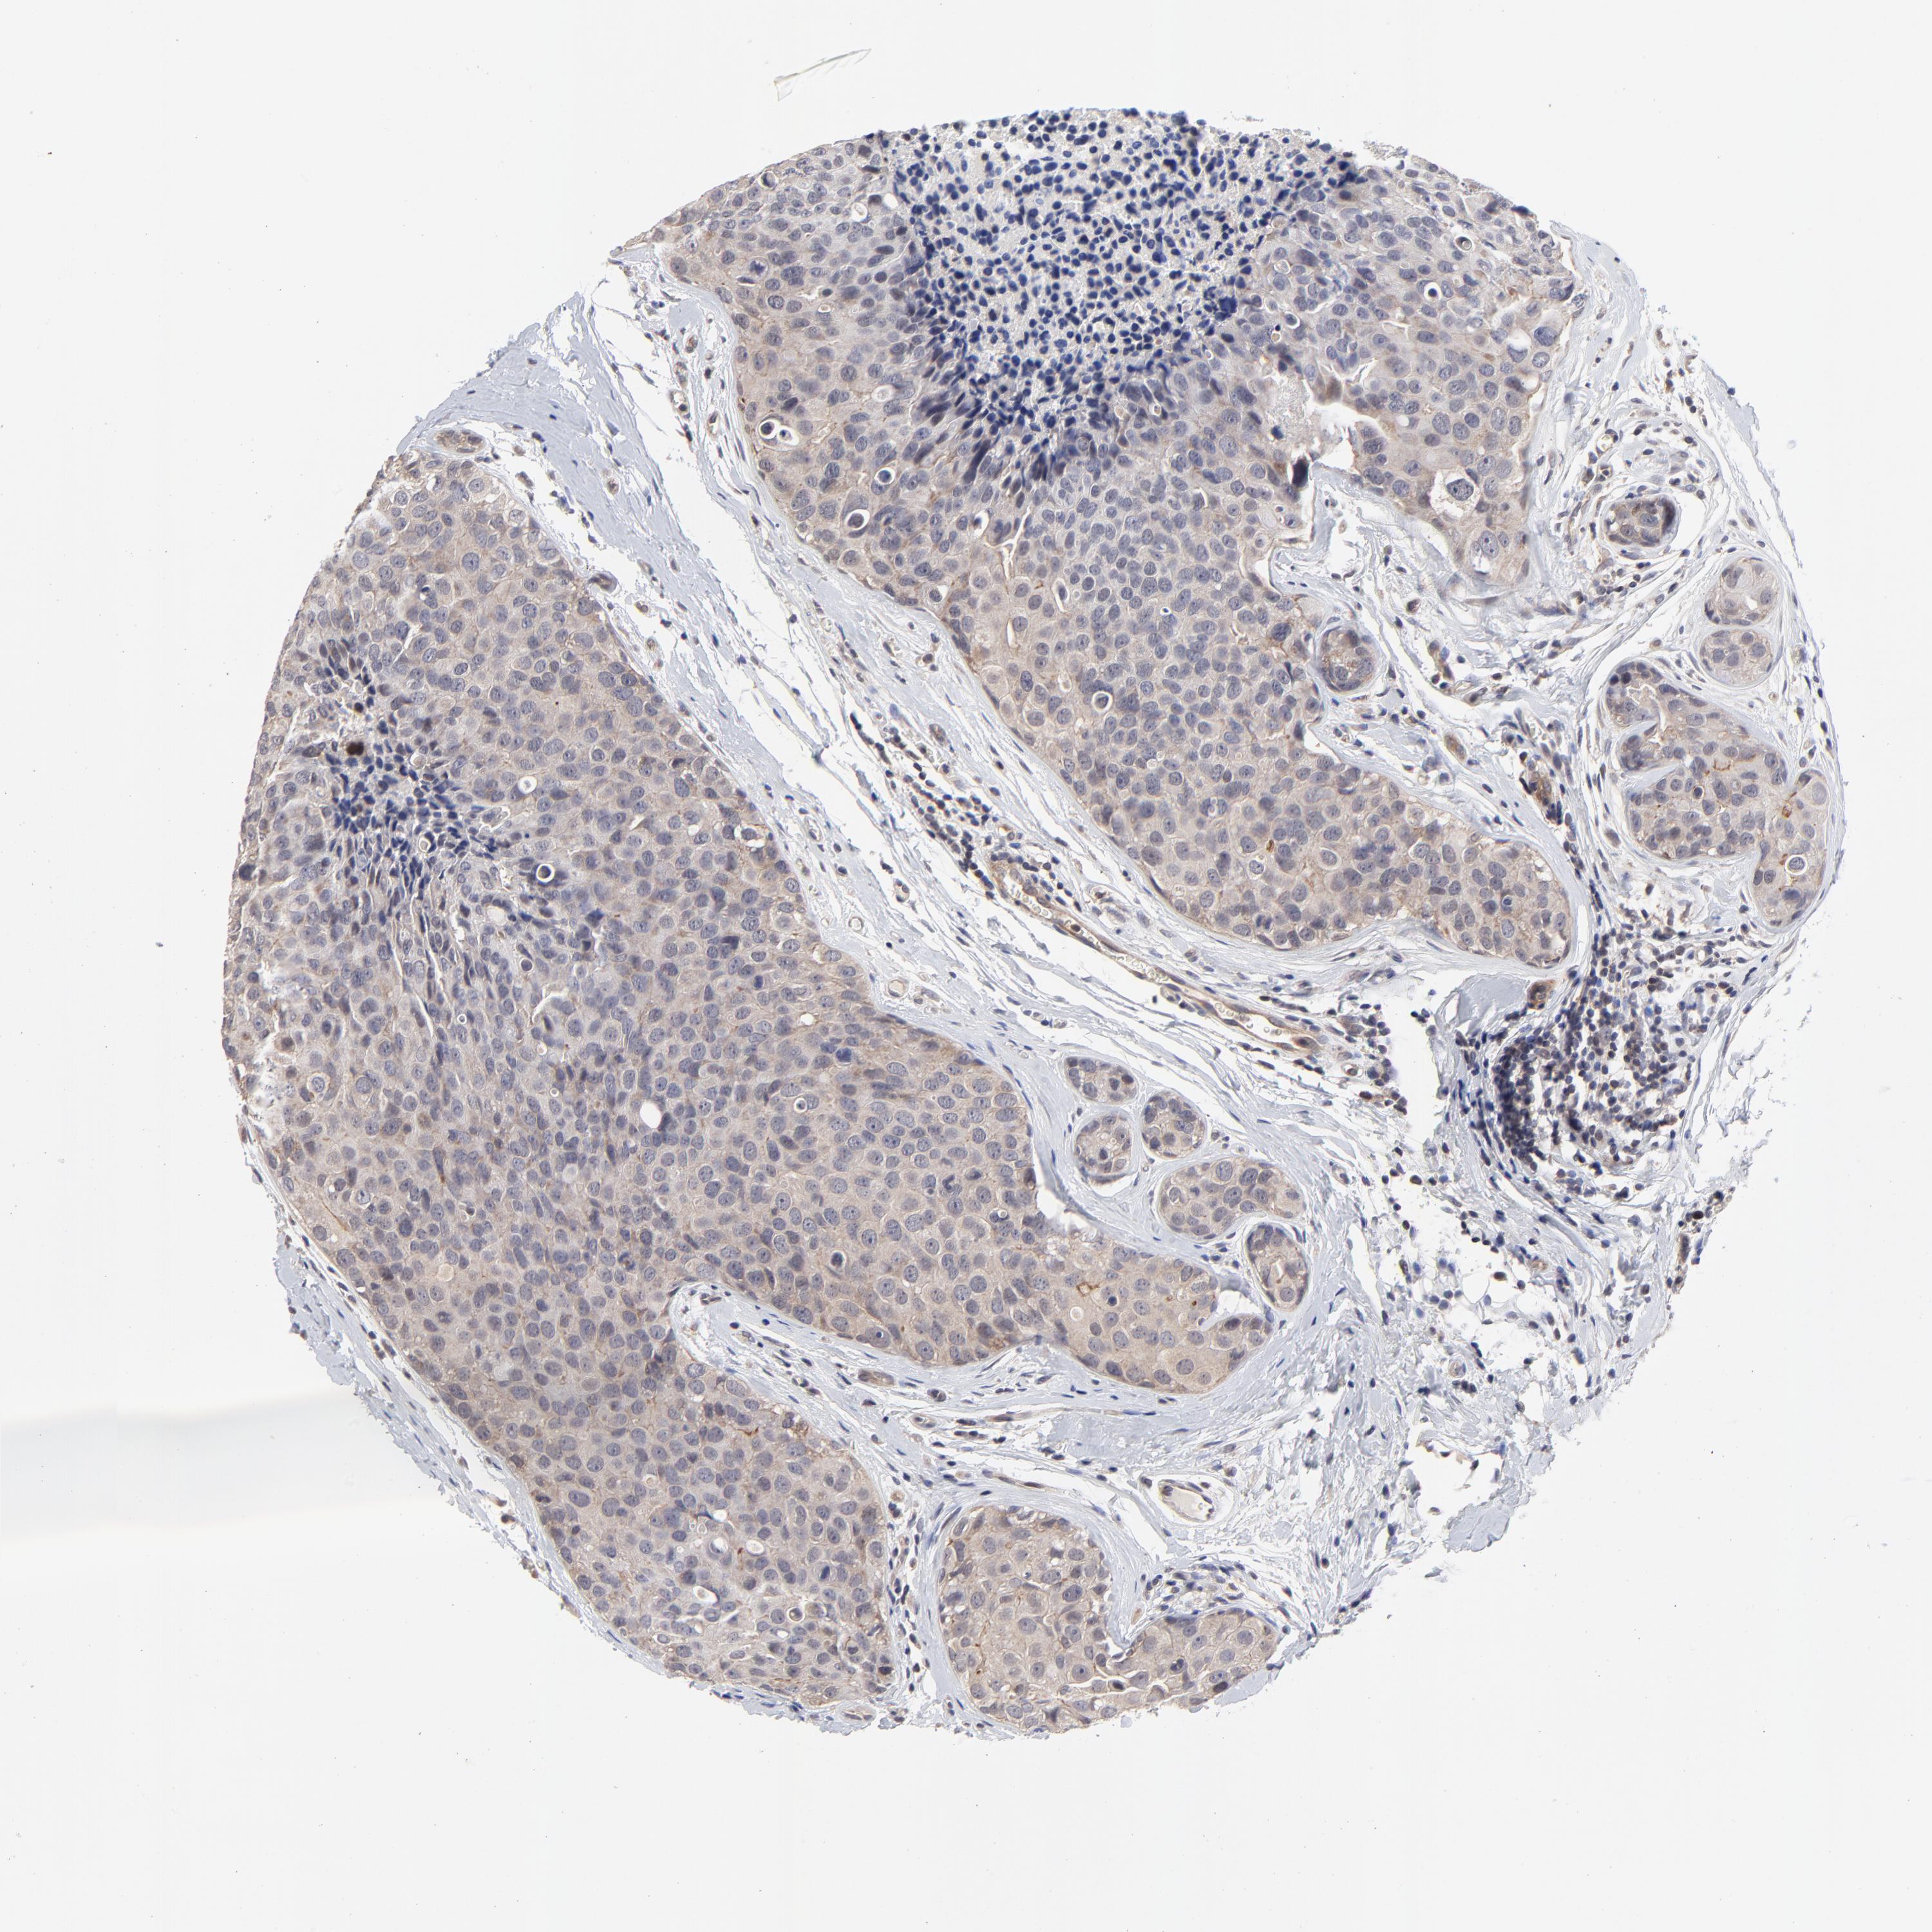

BRCA TCGA BRCA VALIDATION PROTEIN EXPRESSION

ANTIBODIES

AND

VALIDATION